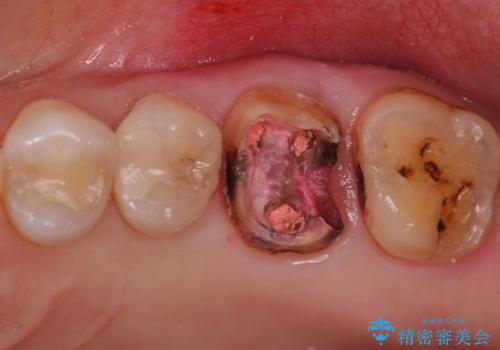

- 検査の結果被せ物の下に虫歯が確認された患者様です。

虫歯を取りきった後セラミッククラウンでの修復処置を行います。

被せ物の裏側の虫歯は被せ物を取らないと除去できません。

今回は過去に治療された部分をすべてやり直しました。

再治療にならないような精密な治療が重要です。